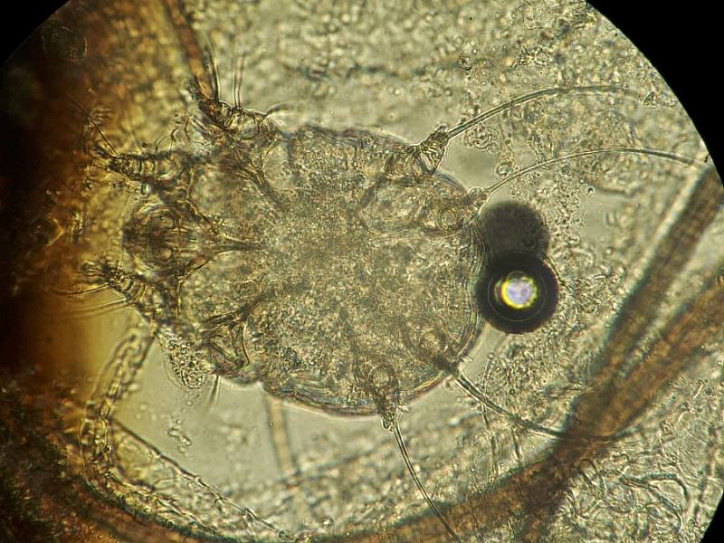

В начале августа к нам в филиал на Свердловском, 18а обратилась молодая пара с маленьким котёнком. При визуальном осмотре стало понятно, что у животного проблемы с шёрстным покровом. На приёме у врача Екатерина (хозяйка котёнка) рассказала, что котика они взяли с рук два дня назад у соседки по саду. Несмотря на поражения у котёнка, которые уже были, молодых людей этот факт не остановил, тем более им сказали, что это не заразно, а так проявляется аллергия на корм. В результате осмотра наблюдались очаги поражения на голове, вблизи ушей. Постоянно почёсывая поражённые места, котик разносил паразитов по всему телу. Вскоре шёрстка начала выпадать, особенно это хорошо было заметно на голове. На голых участках видны коросты. Ко всему прочему, у котика были обнаружены блохи. На приеме животного врачом были взяты анализы крови, соскобы на дерматофитоз (грибковое заболевание) и арахноэнтомоз (паразитарное). При микроскопическом исследовании соскобов с кожи был обнаружен возбудитель паразитарного заболевания – подкожный чесоточный клещ Sarcoptes scabiei, а также споры грибков в и поставлен диагноз – саркоптоз, дерматофитоз, блошиный дерматит.

Возбудители саркоптоза - крошечные паразиты, длина их тельца варьирует от 0,2 до 0,4 мм - питаются эпидермисом, доставляя питомцу дискомфорт и болевые ощущения. Благодаря наличию хоботка клещи прогрызают отверстия в коже и проделывают внутри множество ходов. Они не могут существовать вне тела хозяина размножаться. Одной из главных опасностей патологии считается высокая скорость размножения паразитов. Заметив первые признаки болезни, не стоит откладывать визит к ветеринару.